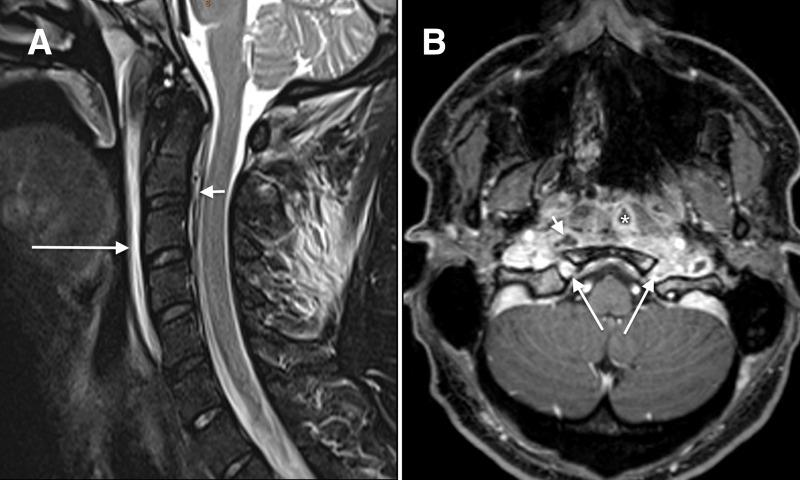

Sphenoid sinusitis is a clinically important entity as it may be associated with catastrophic complications including cavernous sinus thrombosis (CST), cerebral abscess or infarction, meningitis, base of skull osteomyelitis and cranial nerve palsies. We report a case of occult sphenoid sinusitis presenting as bacteraemia, bilateral jugular vein and CST, cranial nerve palsy and base of skull osteomyelitis.

蝶窦炎是一种临床重要的病症,因为它可能与灾难性并发症相关,包括海绵窦血栓形成(CST)、脑脓肿或梗死、脑膜炎、颅底骨髓炎和颅神经麻痹。我们报告了一例隐匿性蝶窦炎病例,表现为菌血症、双侧颈内静脉和 CST、颅神经麻痹和颅底骨髓炎。